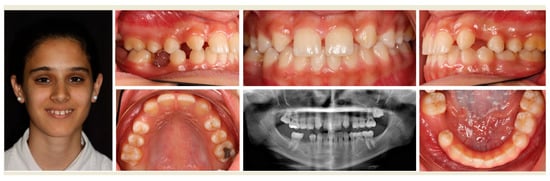

- To demonstrate the clinical management of agenesis of maxillary lateral incisors specifically, because of esthetic concerns, and that of missing second premolars.